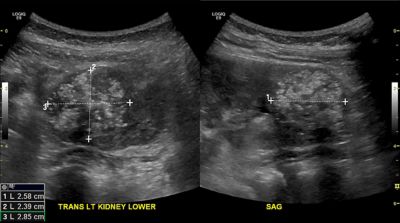

УЗИ саркомы мягких тканей

— Осмотр опытного специалиста, врача-онколога; На фото можно увидеть, как выглядит саркома мягких тканей — УЗИ опухолей мягких тканей . Это метод диагностики как первичного очага, так и поражения региональных зон .

Ультразвуковая картина липомы и липосаркомы довольно сильно отличается . Основное отличие - наличие активного кровотока в ткани Липосаркома на УЗИ: имеет нечёткий (размытый) и неровный контур, в подавляющем большинстве случаев состоит из участков . . .

УЗИ с помощью ультразвуковых волн специалист может отличить уплотнения от обычных кист - заполненных жидкостью мешочков . При подозрении на саркому мягких тканей врач назначает биопсию, в ходе которой небольшой кусочек опухоли изымается и передается в . . .

УЗИ саркомы мягких тканей . УЗИ диагностика является один из самых распространенных методов, позволяющих установить размеры и Томограф дает очень четкое представление о наличие опухолей во внутренних органах и обнаруживает даже очень маленькие очаги . . .